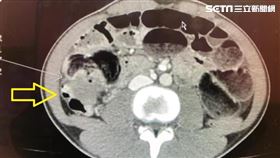

20多歲年輕人腹脹2週 竟是大腸癌

近年來隨著生活習慣的改變和飲食形式多元化,我國大腸直...